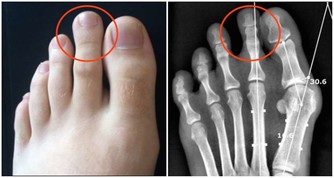

4、會使骨質疏鬆症的可能性變高,同時過多攝入膽固醇可導致牙周病、牙和牙隙之間的溝隙會擴大。